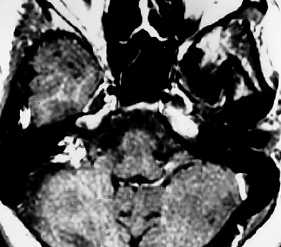

МР-сканирование головного мозга с прицельным изучением мосто-мозжечкового угла, фронтальный срез

«Окрашивающий» раствор заполняет просвет вен и артерий, межклеточное пространство в исследуемой зоне. На снимках появляется четкий рисунок сети кровеносных сосудов, хорошо видны аномалии строения (петли, анастомозы, аневризмы и пр.), определяется зона компрессии корешка черепно-мозгового нерва при вазоневральном конфликте.

При использовании контраста МРТ визуализирует новообразования, диаметр которых не превышает 3 мм. Ткани опухоли накапливают усиливающий препарат, сосудистая сеть, в зависимости от степени малигнизации (озлокачествления), имеет характерный рисунок. На основании полученных изображений рентгенолог может предположить характер процесса, окончательный диагноз ставит лечащий врач.

Новообразование в области мосто-мозжечкового угла (фронтальная проекция)